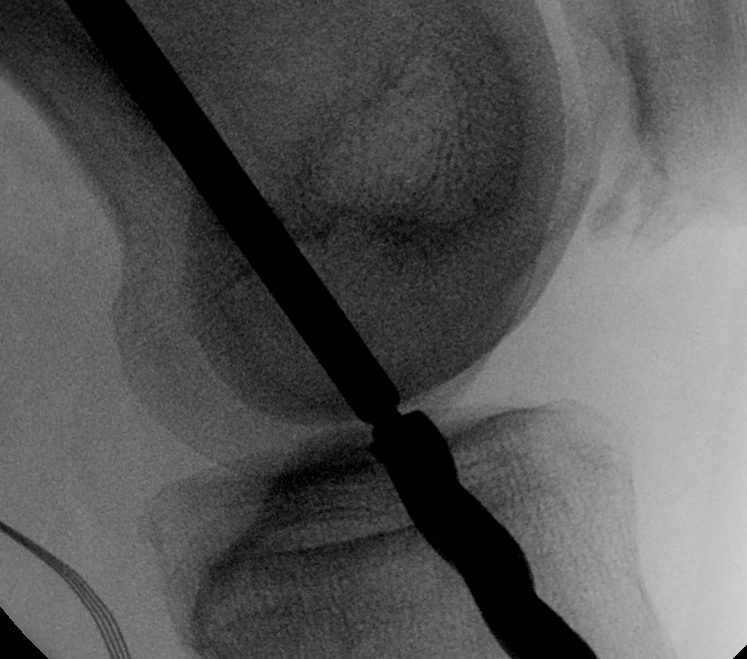

- II with perfect lateral of knee

- superimposed femoral condyles

Femoral entry point

- place beath pin just medial to patella tendon

- insert into femoral insertion of ACL on LFC

- check entry on lateral

- imagine posterior femoral condyle as circle

- entry point in centre, but 60% of distance posterior

- can also look inside knee with scope to confirm insertion

- drive out lateral femur as standard

- pull pin back through femur so that guide wire passes up into femur

- distal pin now in joint